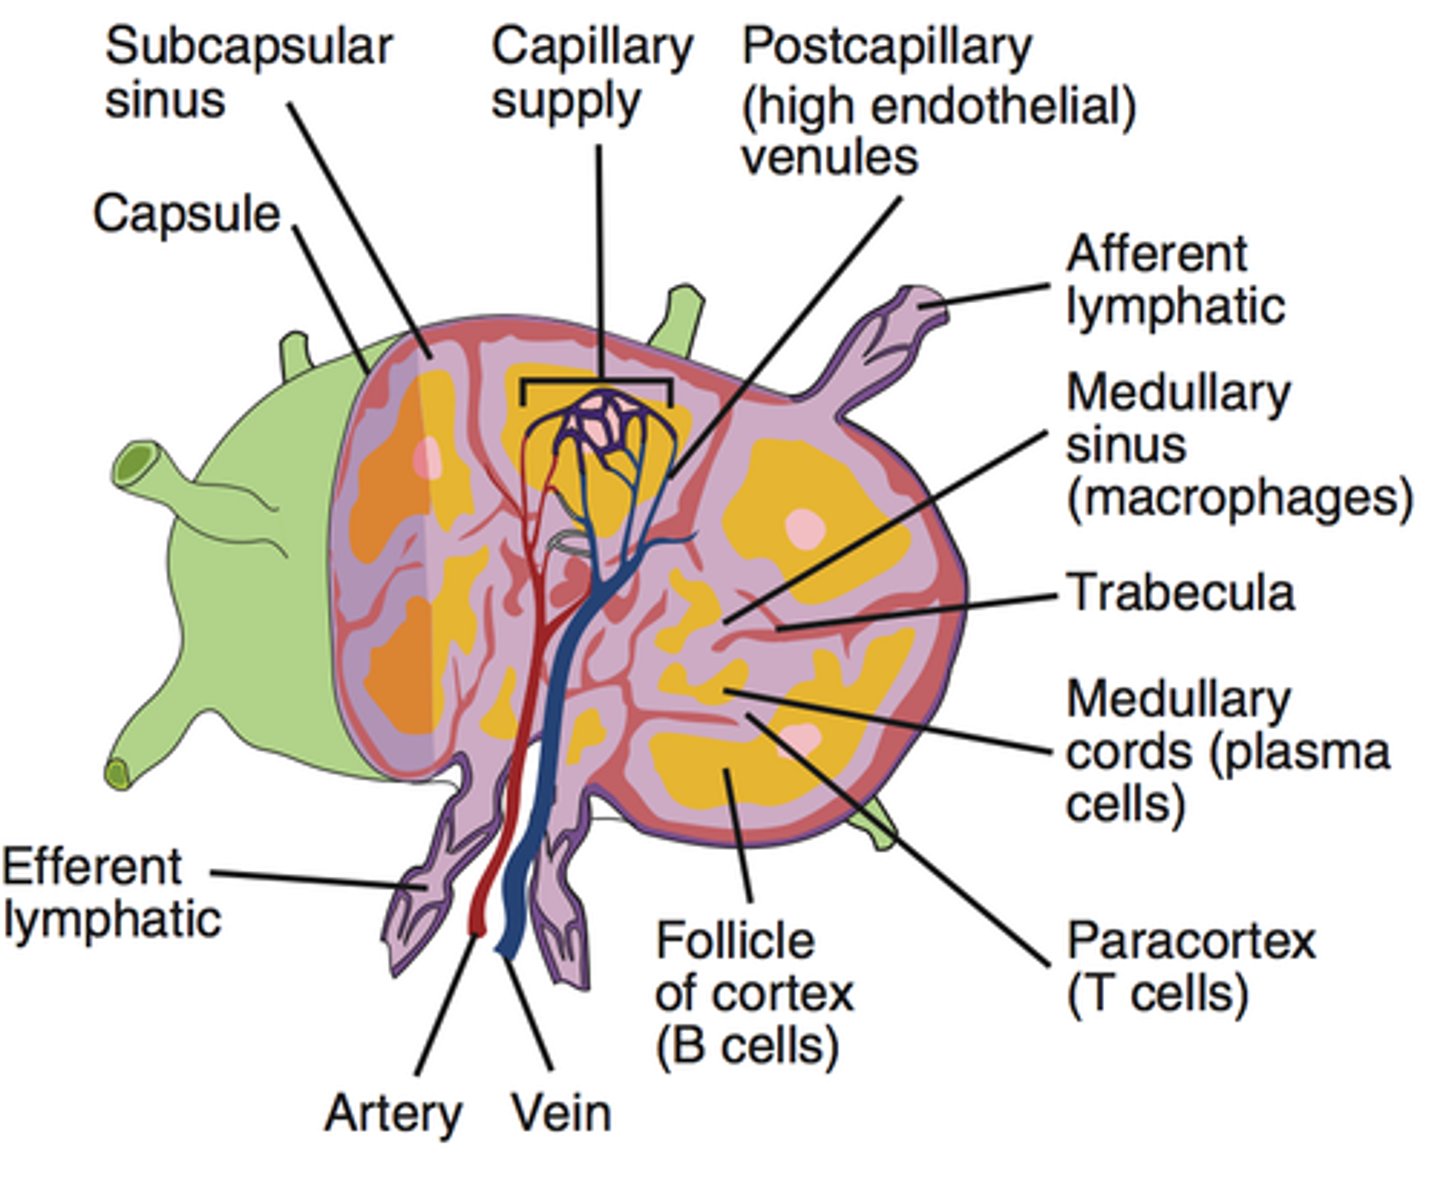

Secondary lymphoid tissues

Lymph nodes, spleen, and mucosa-associated lymphoid tissue (MALT)

What do the lymph nodes do?

Filter lymph --> trap pathogens for destruction by white blood cells

Lymphocytes

Structure: Has a large, dark purple nucleus that takes up most of the cell volume

Function: B cells make antibodies, T cells fight off viral infections, NK cells

B cells

A type of lymphocyte that is created in the bone marrow; creates antibodies that isolate and destroy pathogens

Plasma cells

A type of effector B cells, they produce antibodies

T cells

A type of lymphocyte that is created in the thymus; produce substances that attack infected cells in the body

Natural Killer (NK) cells

A type of lymphocyte found in the blood/lymph nodes/spleen --> they kill cancer cells and cells infected with viruses